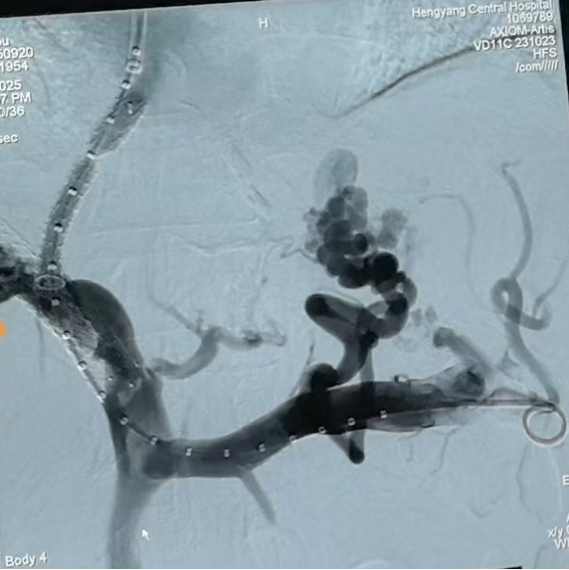

圖一:TIPS術(shù)中

第三步,手術(shù)實施與術(shù)后管理。9月20日,在消化介入團隊精湛操作下,成功為患者實施TIPS支架修補術(shù)。術(shù)中,團隊克服了患者肝內(nèi)血管結(jié)構(gòu)因既往手術(shù)和肝硬化而異常復(fù)雜等諸多困難,精準(zhǔn)地在門靜脈與肝靜脈之間建立了有效分流,并置入覆膜支架以確保分流道長期通暢。術(shù)后門靜脈壓力即刻顯著下降,達到了預(yù)期血流動力學(xué)目標(biāo)。

圖二:TIPS術(shù)中影像